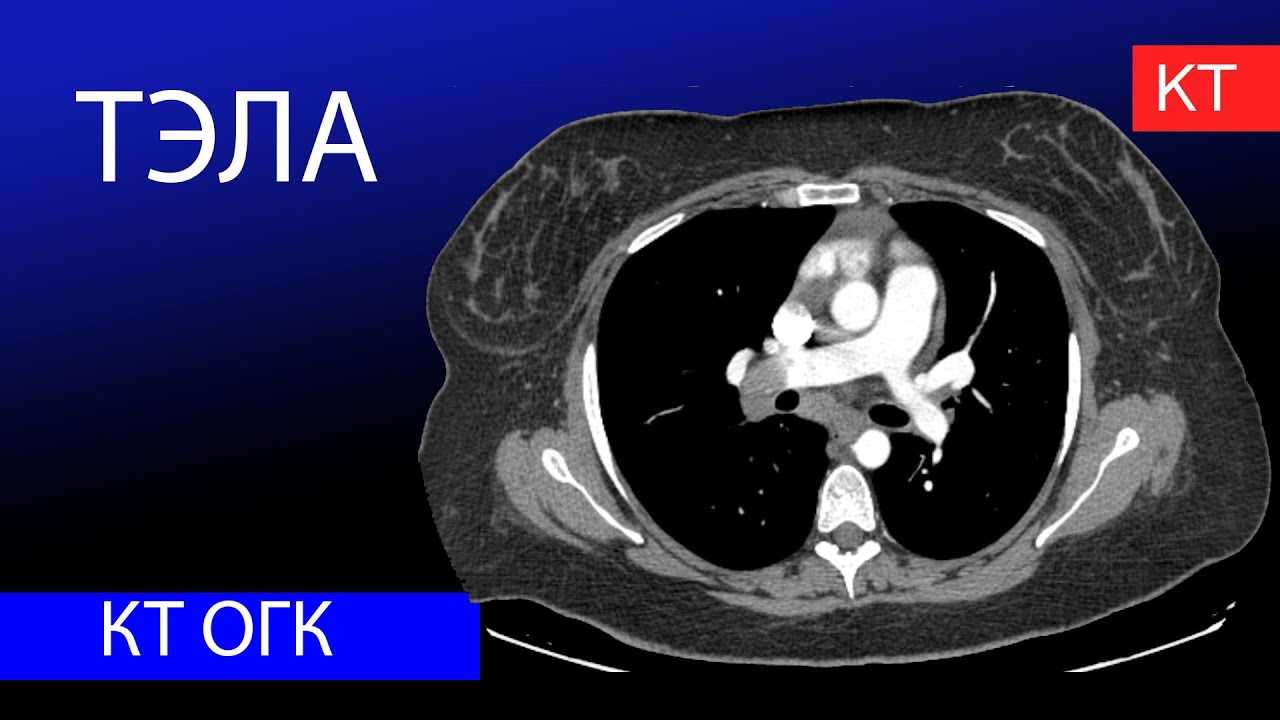

Тэла и пневмония